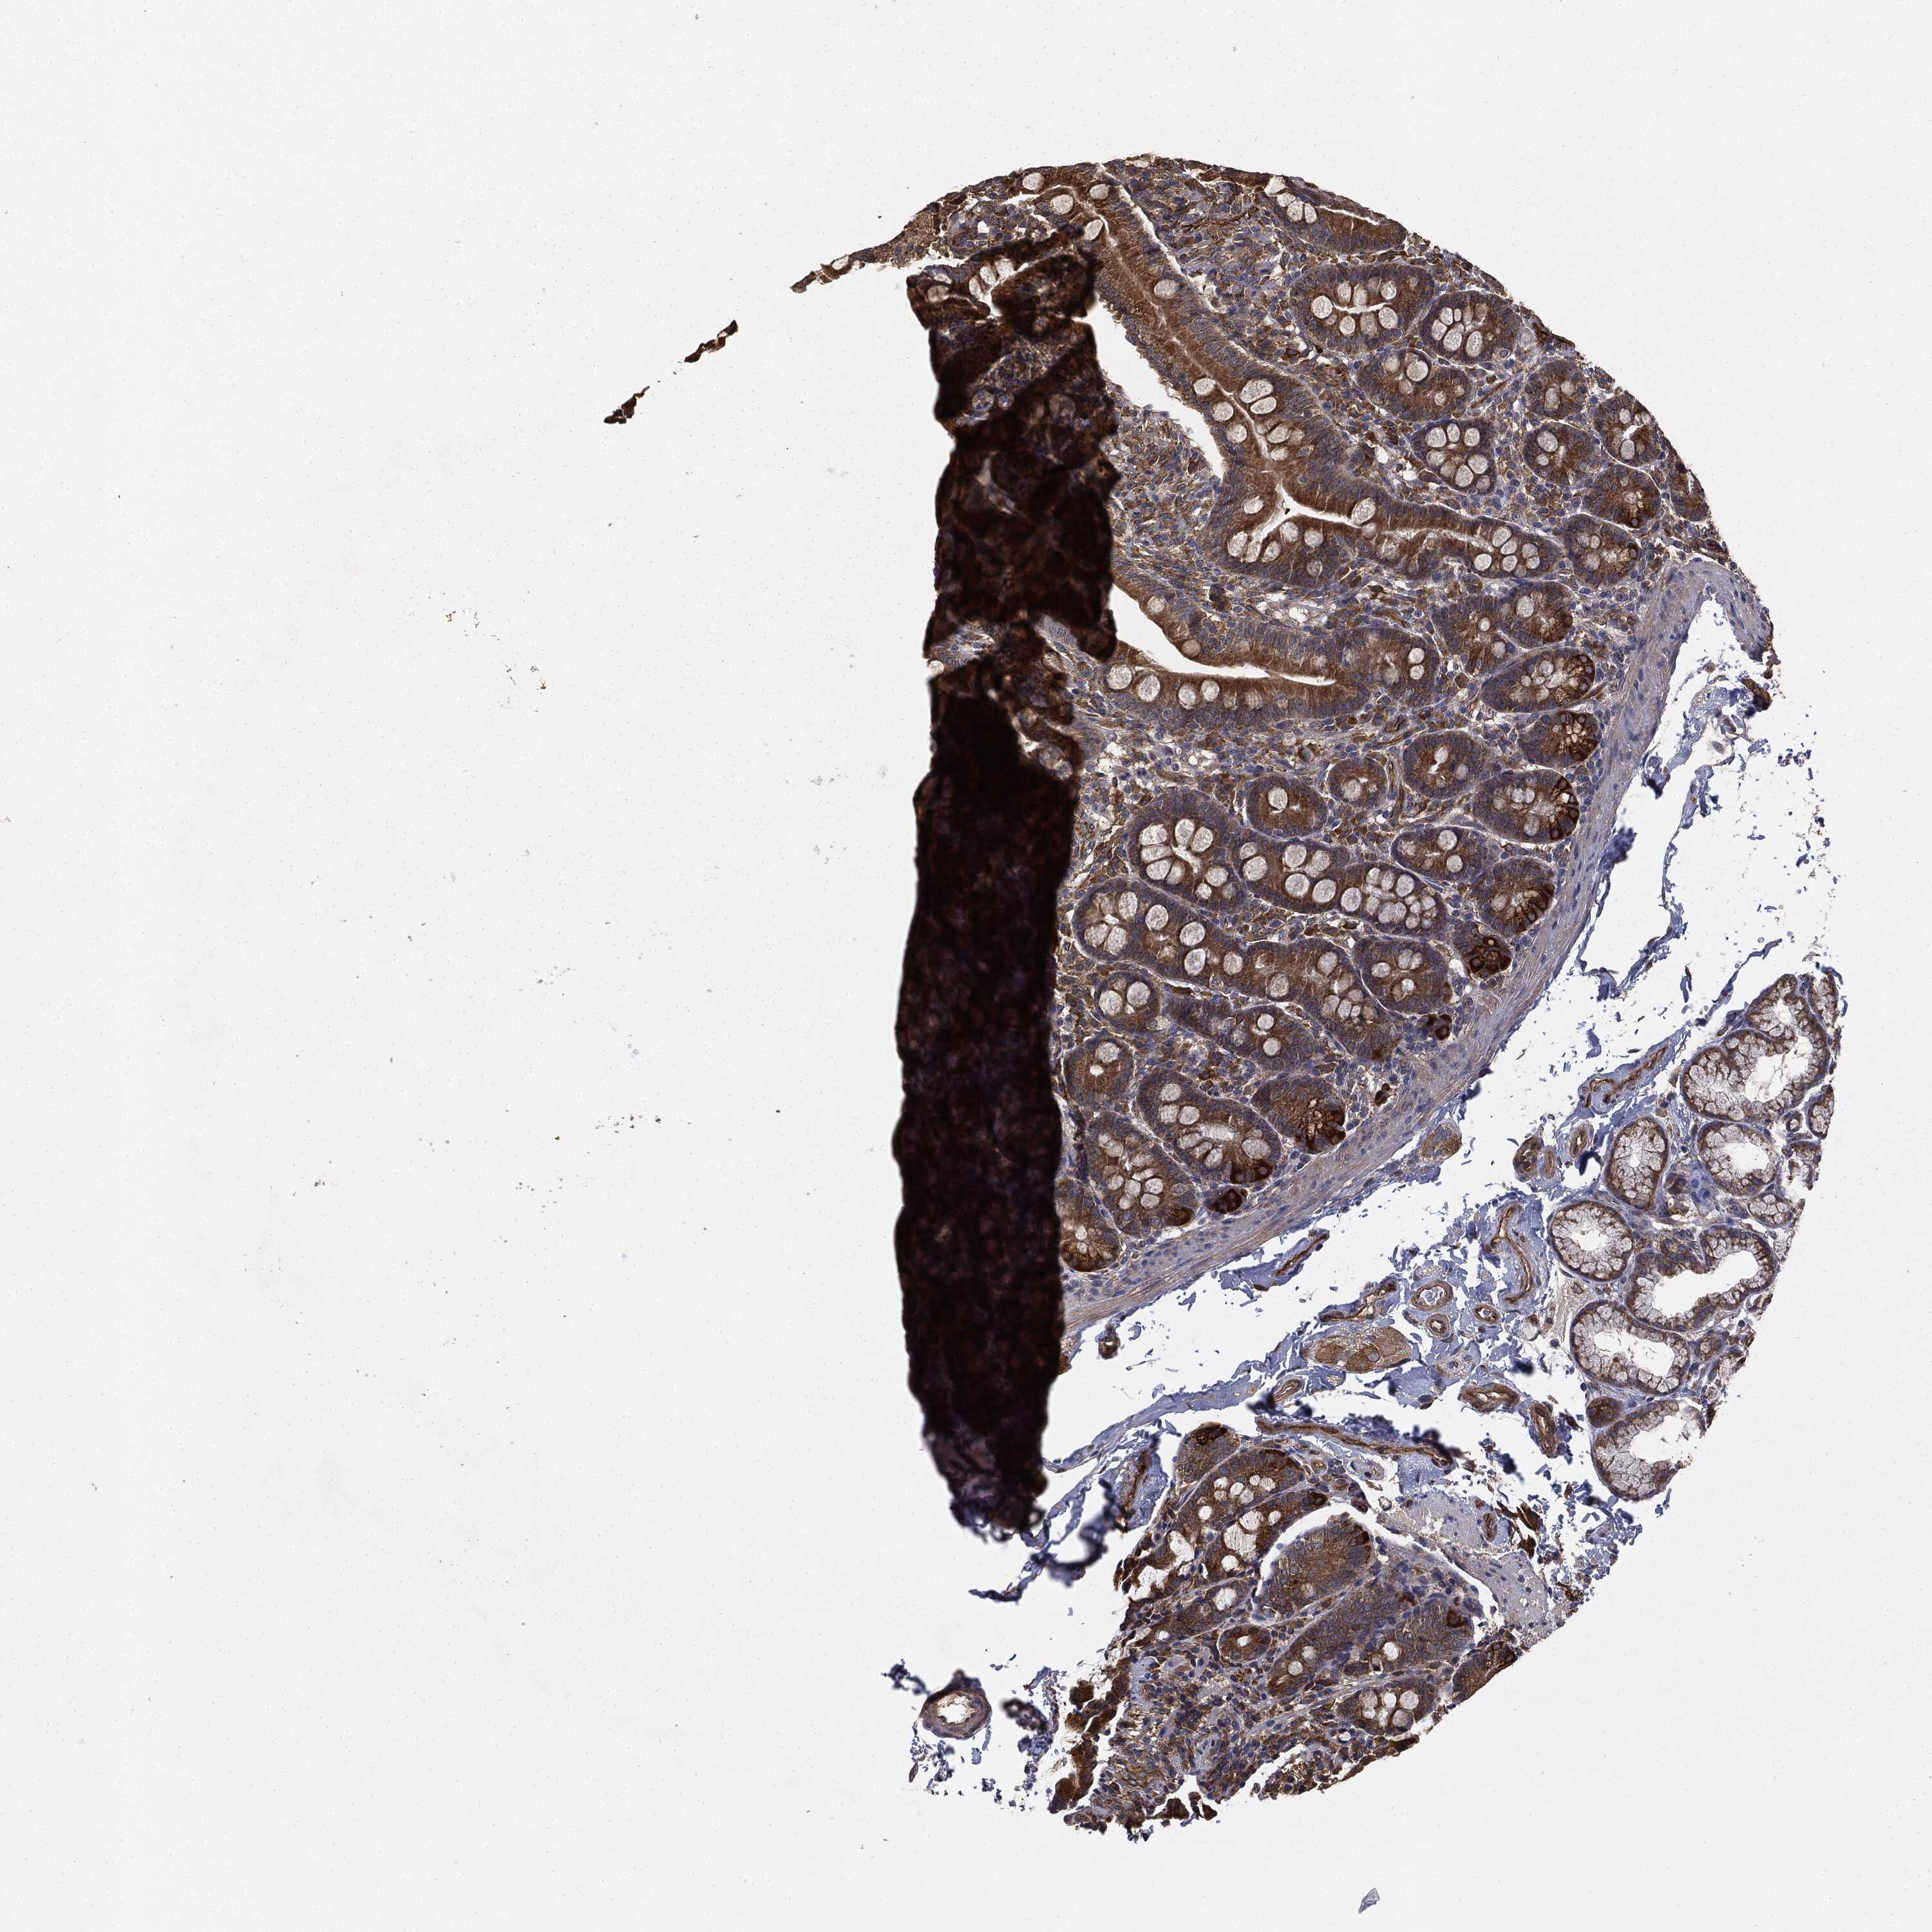

SMALL INTESTINE - Antibody stainingi

Antibody staining in the annotated cell types in the current human tissue is reported as not detected, low, medium, or high, based on conventional immunohistochemistry profiling in selected tissues. This score is based on the combination of the staining intensity and fraction of stained cells.

Each image is clickable and will lead to virtual microscopy that enables deeper exploration of all samples and also displays staining intensity scores, fraction scores and subcellular localization as well as patient and tissue information for each sample.

Antibody HPA041439Antibody HPA066153

Glandular cells MediumHigh